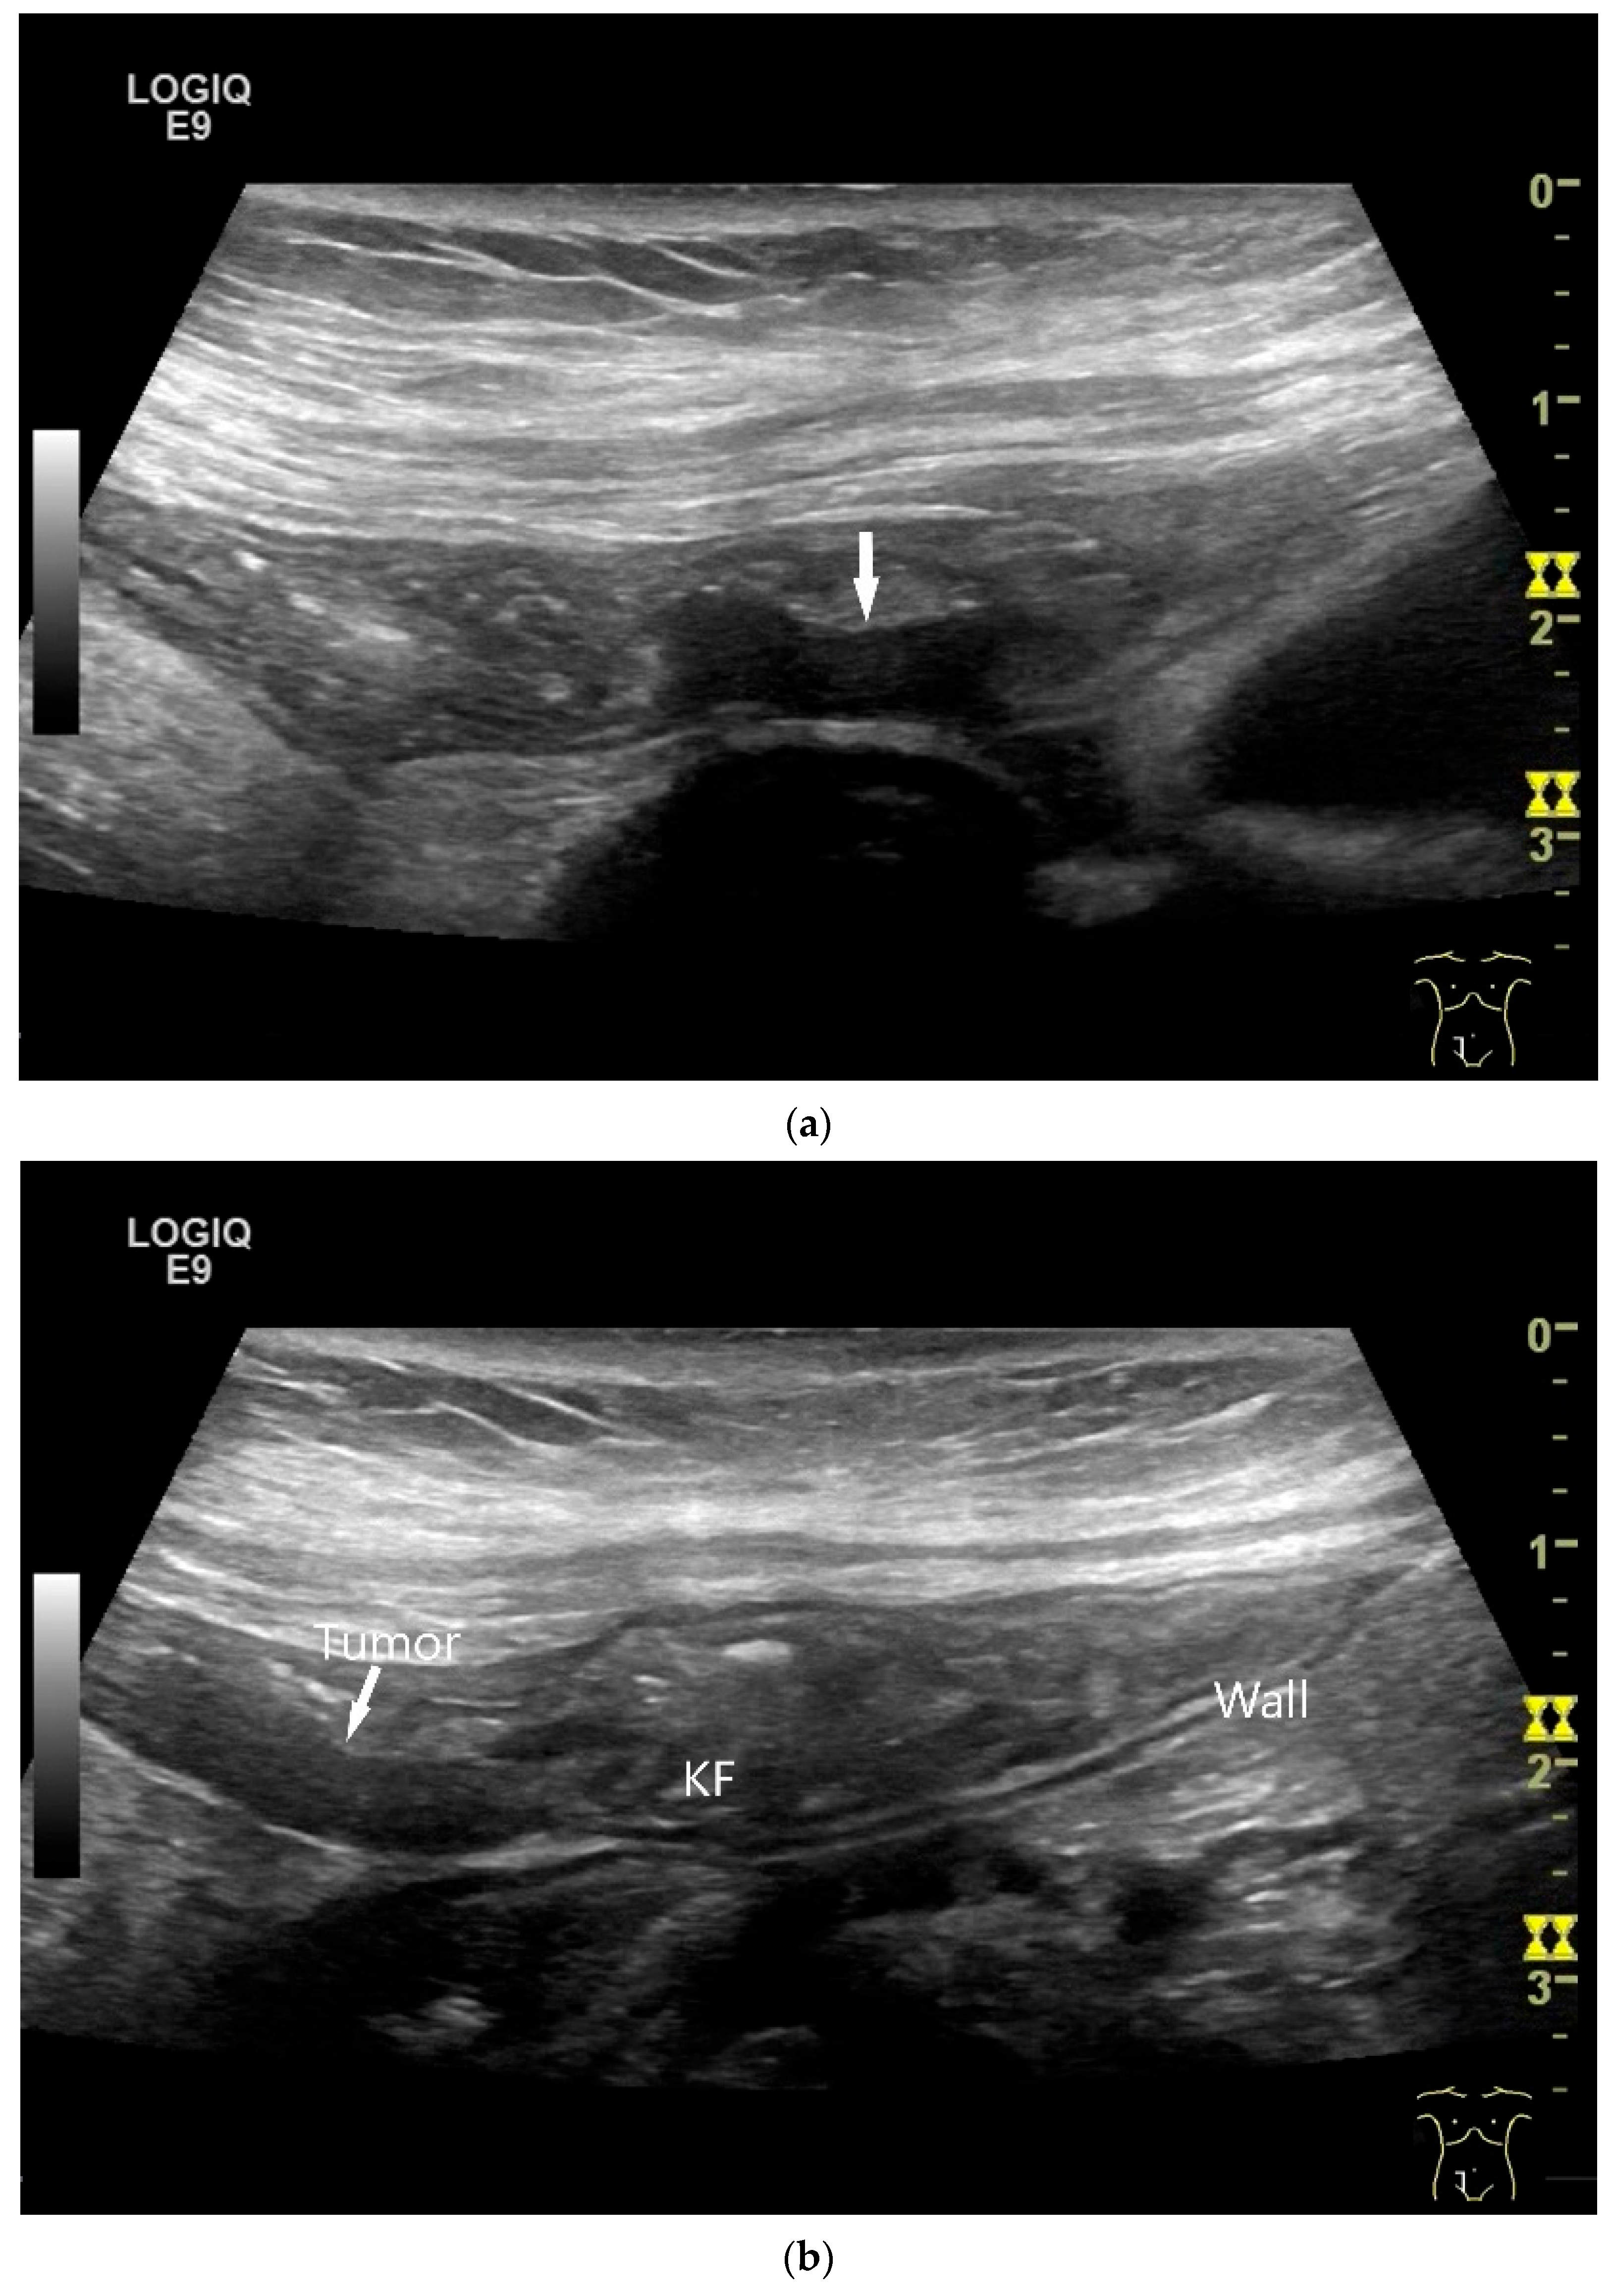

Figure 8.

NET in the ileum. In the terminal ileum, there is a slight wall thickening <5 mm (arrow), but with loss of stratification (a). The tumor (arrow) changes position with peristalsis while the transducer position remains the same. With the 9 MHz linear transducer, the five layers of the unremarkable wall and Kerckring folds (KF) are visible (b). Small vessels can be distinguished in power Doppler (c).

On US, small intestine NEN appear as small focal hypoechoic wall thickenings with a pseudo nodular appearance or as hypoechoic nodular lesion. They are usually small tumors. Adjacent pathological lymph nodes may appear in the mesentery. The tumors extend from the submucosa and may extend into the mesentery via the lamina muscularis propria [90,91,92,93,94,95,96]. NEN are usually well vascularized. Color Doppler imaging (CDI) can show irregular macrovessels in the tumor. Case reports showed that small intestine NETs are hyperenhanced on CEUS [91,92,94,95,96,97] (Figure 7 and Figure 8). Further diagnostics include CT and DOTATOC-PET.